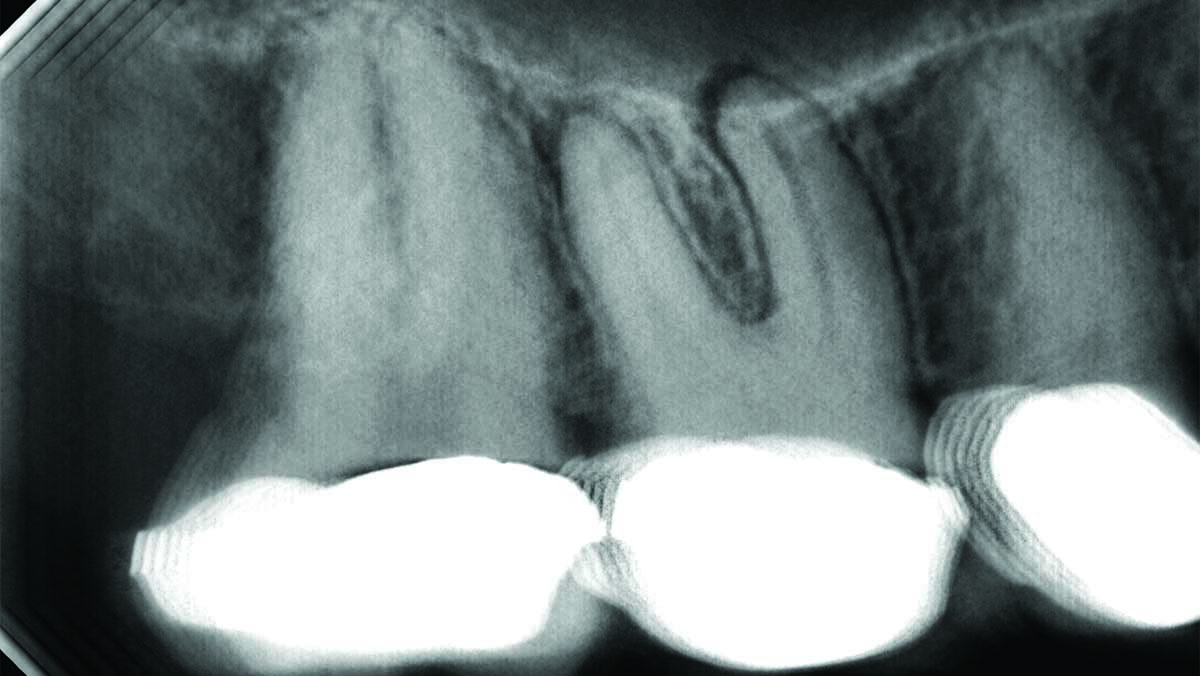

The most common odontogenic infection is that of the periapical tissues most frequently caused by dental caries, a deep restoration, or failed root canal treatment.1 Apical periodontitis (AP) has been found to have a prevalence of 50% in patients under the age of 50, and the prevalence and risk of AP has been found to be … Read more